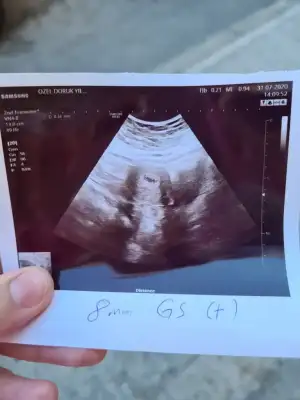

5 haftalık dedi doktor bebek gözükse söylerdi diye düşünüyorum ama bilemedim boş gebelikte hiç bişey yoktu bunda bişey görünce sevindim

5 haftada benimde senin usg gibiydi canımm Allahın izniyle hersey yolunda gider insallah bazen atım duyulmasada usg de görülebiliyor küçük olursa benim önce gördüler cok şükür bugunde duyduk

Benim gibi çizgimi vardı canım heycanlandım şimdi çünkü diğer boş gebelikte bildiğin bomboştu bariz belliydi eşime bi foto attım netten baby yazıyodu o çizgi işaretlenmişti bizim kese sandı çok benziyo dedi ama doktor neden kesen gözüküyo dedi anlamadım inşallah seninde dediğin gibidir bende duyarım senin gibi inşallah

Canım bak buda benim 5+2 bebek gözükmüyor ama yolk kesesi gözüküyor demişti gittiğimiz doktor özel bi hastanenin nöbetçi kadın doğumuna gitmiştim iyi düşün iyi olsun inşallah canım belki doktor seninde yolk kesesini kastetmiştir. Bebeği ilk haftalarda besleyen kese o.

Evet sendede çizgi var içinde☺️ Buna bile seviniyorum artık inşallah güzel olur